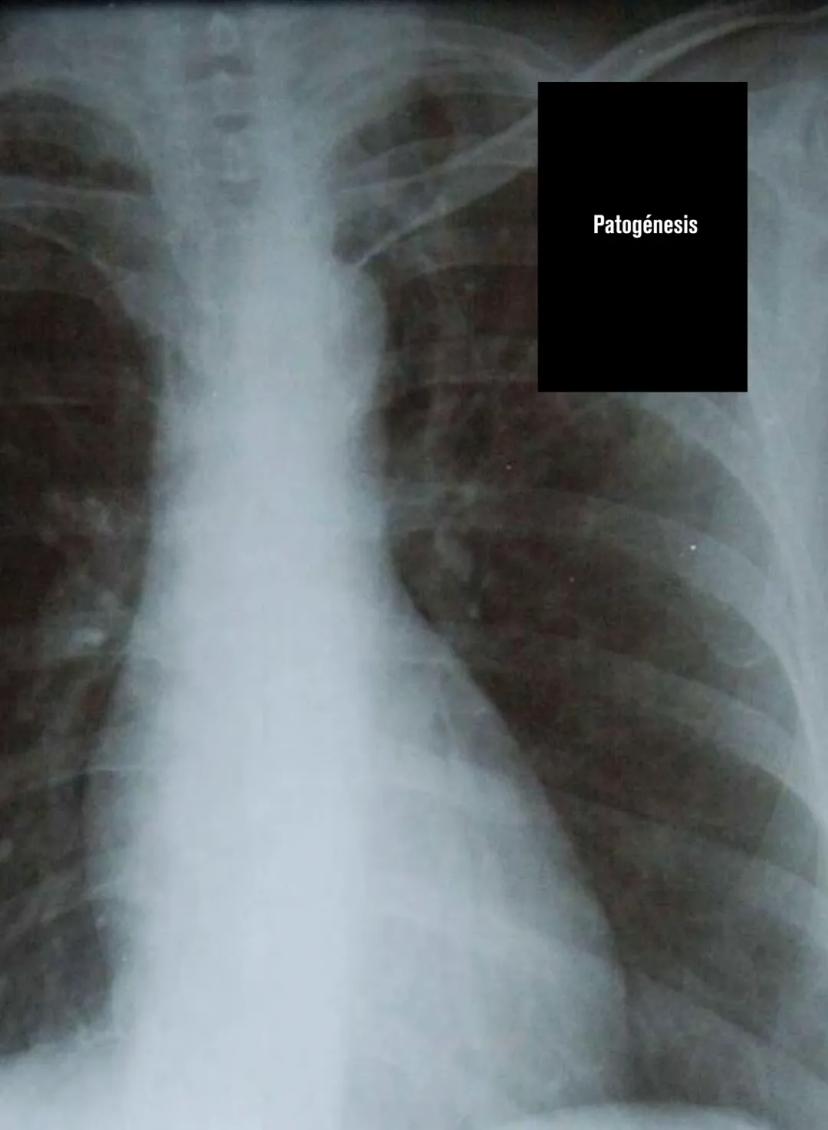

¿Sabías que la tuberculosis es causada por una bacteria súper resistente llamada Mycobacterium tuberculosis o bacilo de Koch? Esta bacteria generalmente ataca los pulmones, causando lo que se conoce como tuberculosis pulmonar, que es el tipo más común que existe.

Los síntomas son bastante específicos y debes reconocerlos: tos con flemas, pérdida de peso, fiebre, sudoración nocturna, cansancio y dolor en el pecho. Lo más preocupante es la hemoptisis (toser sangre), que es una señal de alarma importante.